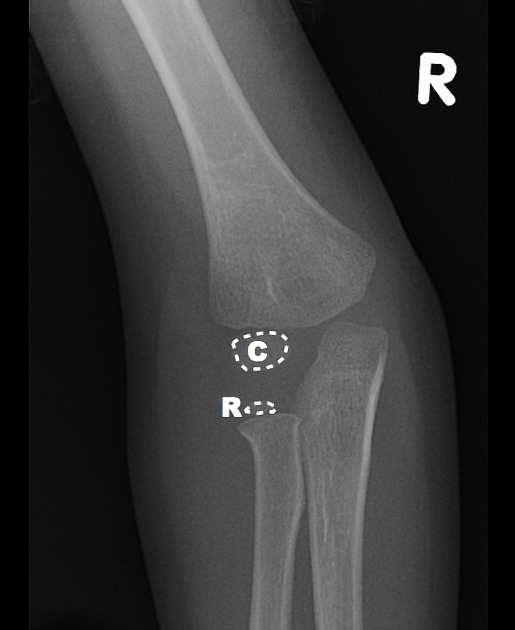

Capitellum

By age one, the capitellum ossifies. On the AP view, imagine a little white oval balloon floating in the darkness between the radius and the humerus.

Radial Head

By age three, the capitellum gets another little balloon to join the party. The radial head is a bony little balloon that floats just above the floor.  If you see both little balloons floating on either ends of the space between the humerus and the radius – you know this child is about three years old.